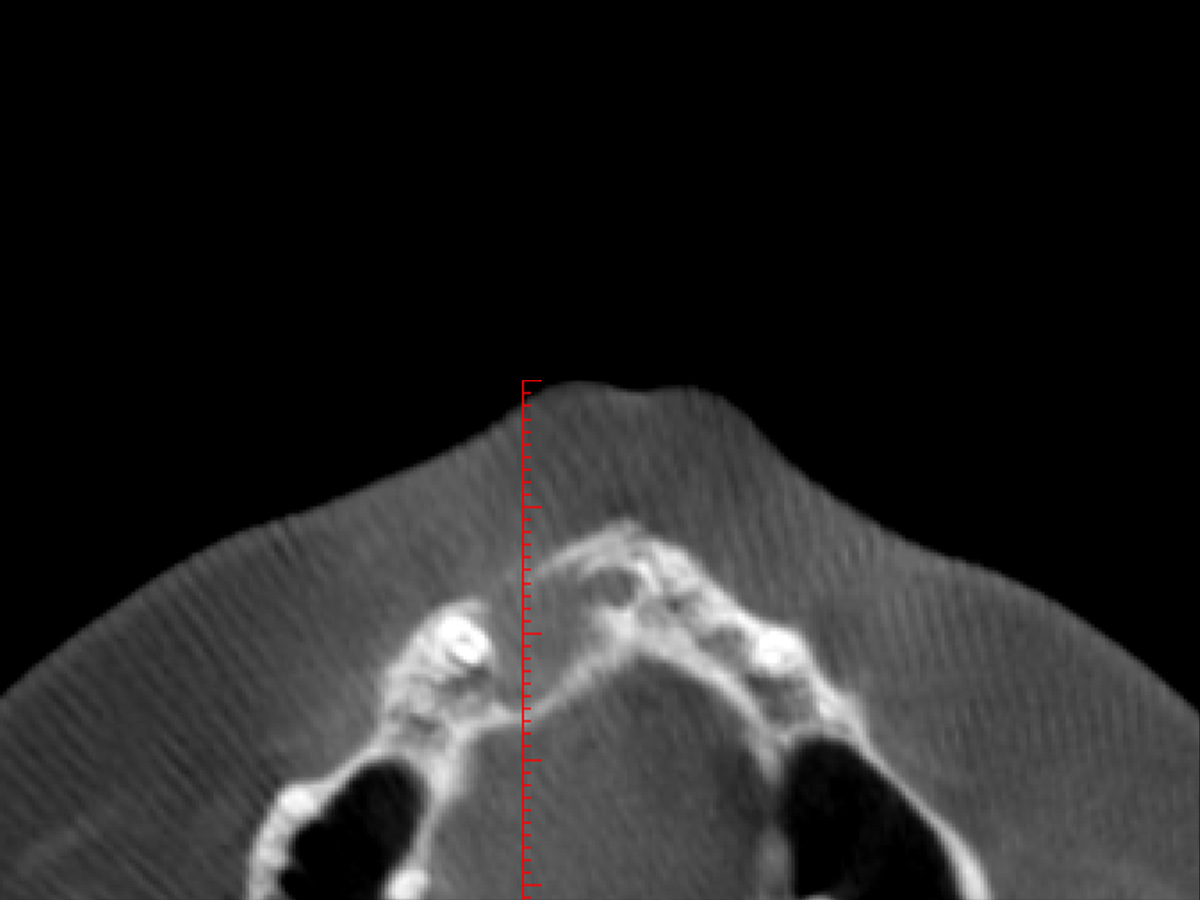

Nach einem Zahntrauma im Jugendalter mit anschließender endodontischer Versorgung stellte sich unsere 24-jährige Patientin mit seit einigen Monaten bestehendem, rezidivierendem Druckgefühl und leichten Schmerzen in regio 11 und 12 vor (Abb. 1, 2, 3). Die klinische Untersuchung ergab an Zahn 11 und 12 Lockerungsgrad 1 und, wie zu erwarten, eine negative Sensitivität. Es lag ein leichter Perkussionsschmerz vertikal wie horizontal vor. Die Krone auf Position 11 zeigte eine leichte Verfärbung im Vergleich zu den Nachbarzähnen. Ein OPG ergab eine – in ihrer Ausdehnung nicht sicher zu beurteilende – Aufhellung im Knochenbereich regio 11 und 12 (Abb. 4). Als Nebenbefund waren teilretinierte Zähne 38 und 48 sowie ein vollständig retinierter Zahn 28 als Mikroform nachzuweisen. Ein zusätzlich durchgeführtes DVT zeigte eine große zystische Formation unter Einschluss der Wurzeln 11 und 12, die vom Canalis nasopalatinus bis mesial 13 mit einer kleineren Perforation zum Nasenboden und größeren Perforationen nach vestibulär und palatinal reichte (Abb. 5, 6, 7).

Abbildung 5

Im DVT ist eine große zystische Formation unter Einschluss der Wurzeln 11 und 12, die vom Canalis nasopalatinus...

Abbildung 6

...bis mesial 13 mit einer kleineren Perforation zum Nasenboden...

Abbildung 7

...und größeren Perforationen nach vestibulär und palatinal reicht.